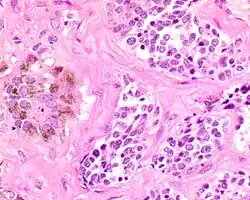

Microscopic

The tumor is usually very well circumscribed but not encapsulated. There are two cell types present (biphasic), arranged in alveolar or tubular configurations.

There are centrally located, small, darkly staining cells comprising the majority of cells. These cells have a fibrillary cytoplasm surrounding round nuclei with coarse and heavy nuclear chromatin. These cells are surrounded by much larger polygonal cells that have open nuclear chromatin and abundant opaque cytoplasm that has granular melanin pigment.

There is usually no hemorrhage, necrosis or increased mitoses.[1][4]